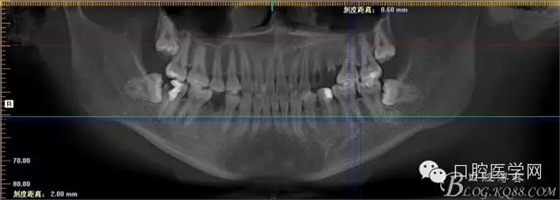

補拍CBCT進行診斷分析

CBCT測量得出根尖囊腫3×4mm,進行常規(guī)根管充填后行根尖切除術(shù)